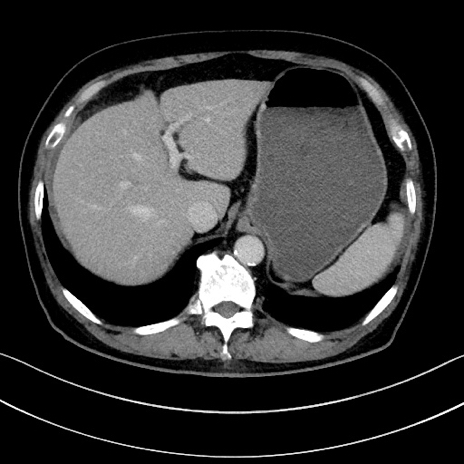

症例15(横断像)

【症例】70歳代男性

【主訴】腹痛

【現病歴】今朝から腹痛あり。全体的に痛い。特に左上の方。排ガスが今日はない。冷や汗が出る。

【既往歴】直腸癌術後

【身体所見】左側腹部〜上腹部に圧痛あり。腹膜刺激症状明らかなではない。軽度反跳痛。左下腹部に術後瘢痕あり。

【データ】WBC 7700、CRP 0.02